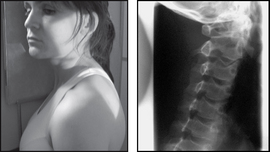

image

Projection: LATERAL

Centring Point: 2.5 cm behind and 5 cm below the angle of the mandible

Projection: ANTERIOR OBLIQUES

Centring Point: To the middle of the cervical spine. Central ray 15° caudal

Points to consider

Technique

image Acute trauma – use horizontal beam – do not adjust head

image Remember to remove jewelry/ear-rings that is in the field of interest

image Exposure made on arrested expiration

image Must include C7 on the radiograph

image Oblique – extend the head back to avoid superimposition of the mandible

Radiological assessment

image Anterior displacement over 3.5 mm – ligaments torn

image Vertebral bodies C3–T1 should be the same size – a disparity of 2 mm may be due to a compression #

image Check all seven vertebrae are seen on the radiograph

image Oblique – demonstrates intervertebral foramina closest to the film (right anterior oblique – right foramina; left anterior oblique – left foramina)

Lateral

Patient in the erect position with the shoulder against the cassette

Median sagittal plane parallel to the cassette

Patient’s shoulders should be relaxed and arms are placed down and slightly behind the trunk

Feet are separated to aid stability

Patient’s chin is raised and extended slightly forwards so that the mandible does not obscure the spine

Collimation

To include: SUPERIORLY: EAM

INFERIORLY: Body T1

LATERALLY: Soft tissue borders

Anterior obliques – both sides for comparison

Patient erect facing a vertical bucky

Trunk is then rotated 45° to each side in turn

Patient’s head is rotated so that the median sagittal plane is parallel to the bucky

As with every x-ray ensure anatomical legends are applied as interpretation without them at times can be confusing